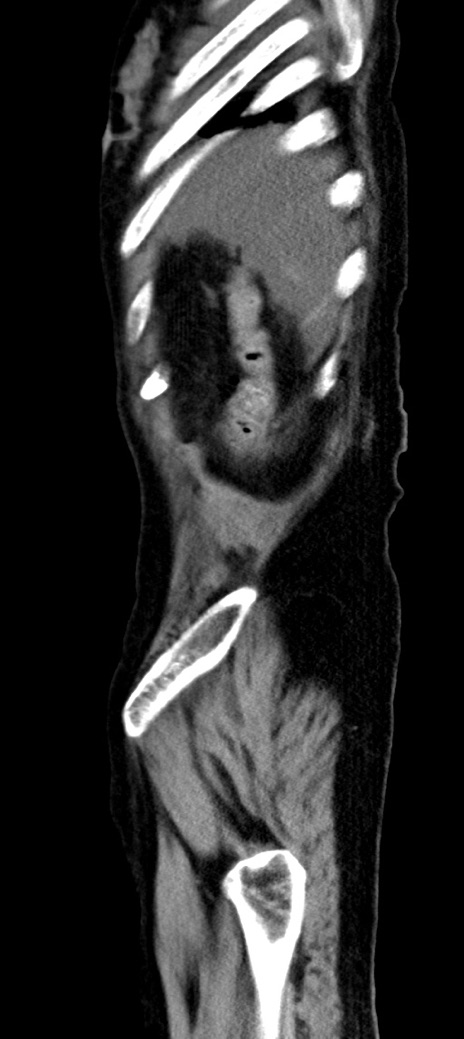

横断像

冠状断像

他院CT